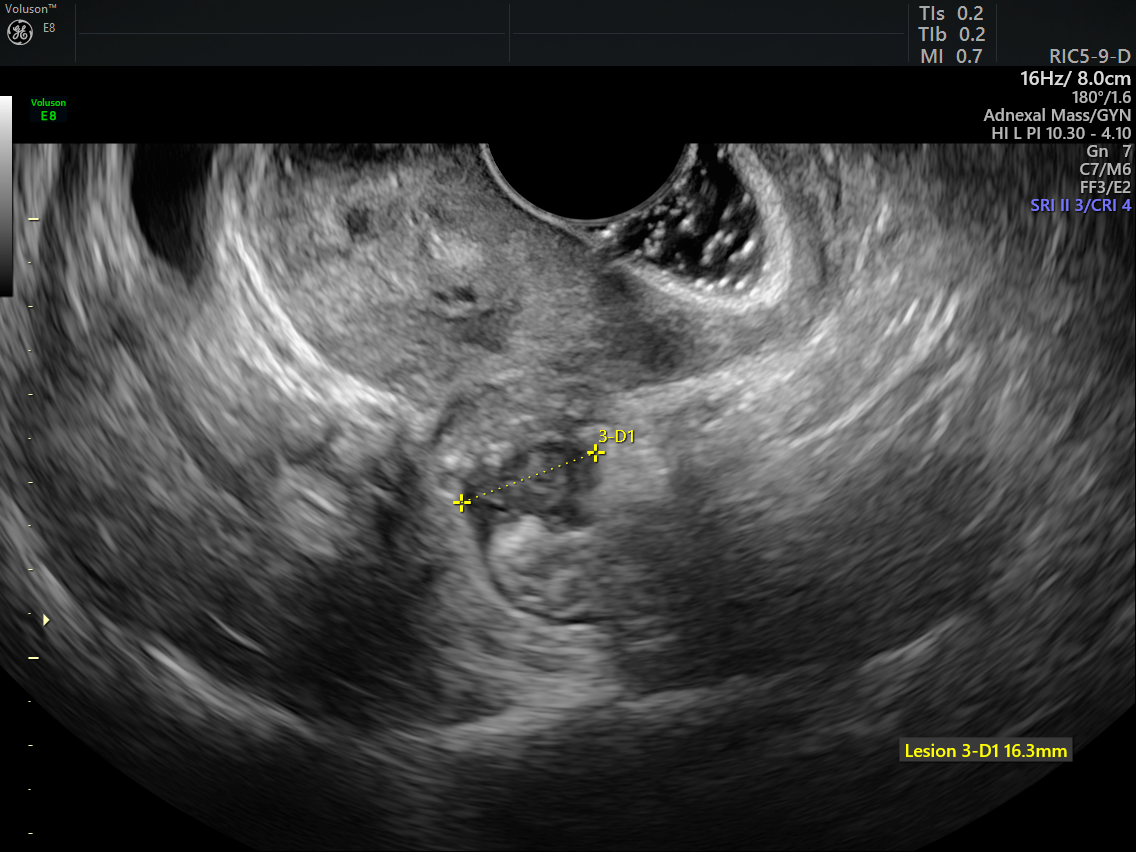

Deep Infiltrating Endometriosis Using Preoperative Radiology For Surgical Planning Journal Of Minimally Invasive Gynecology